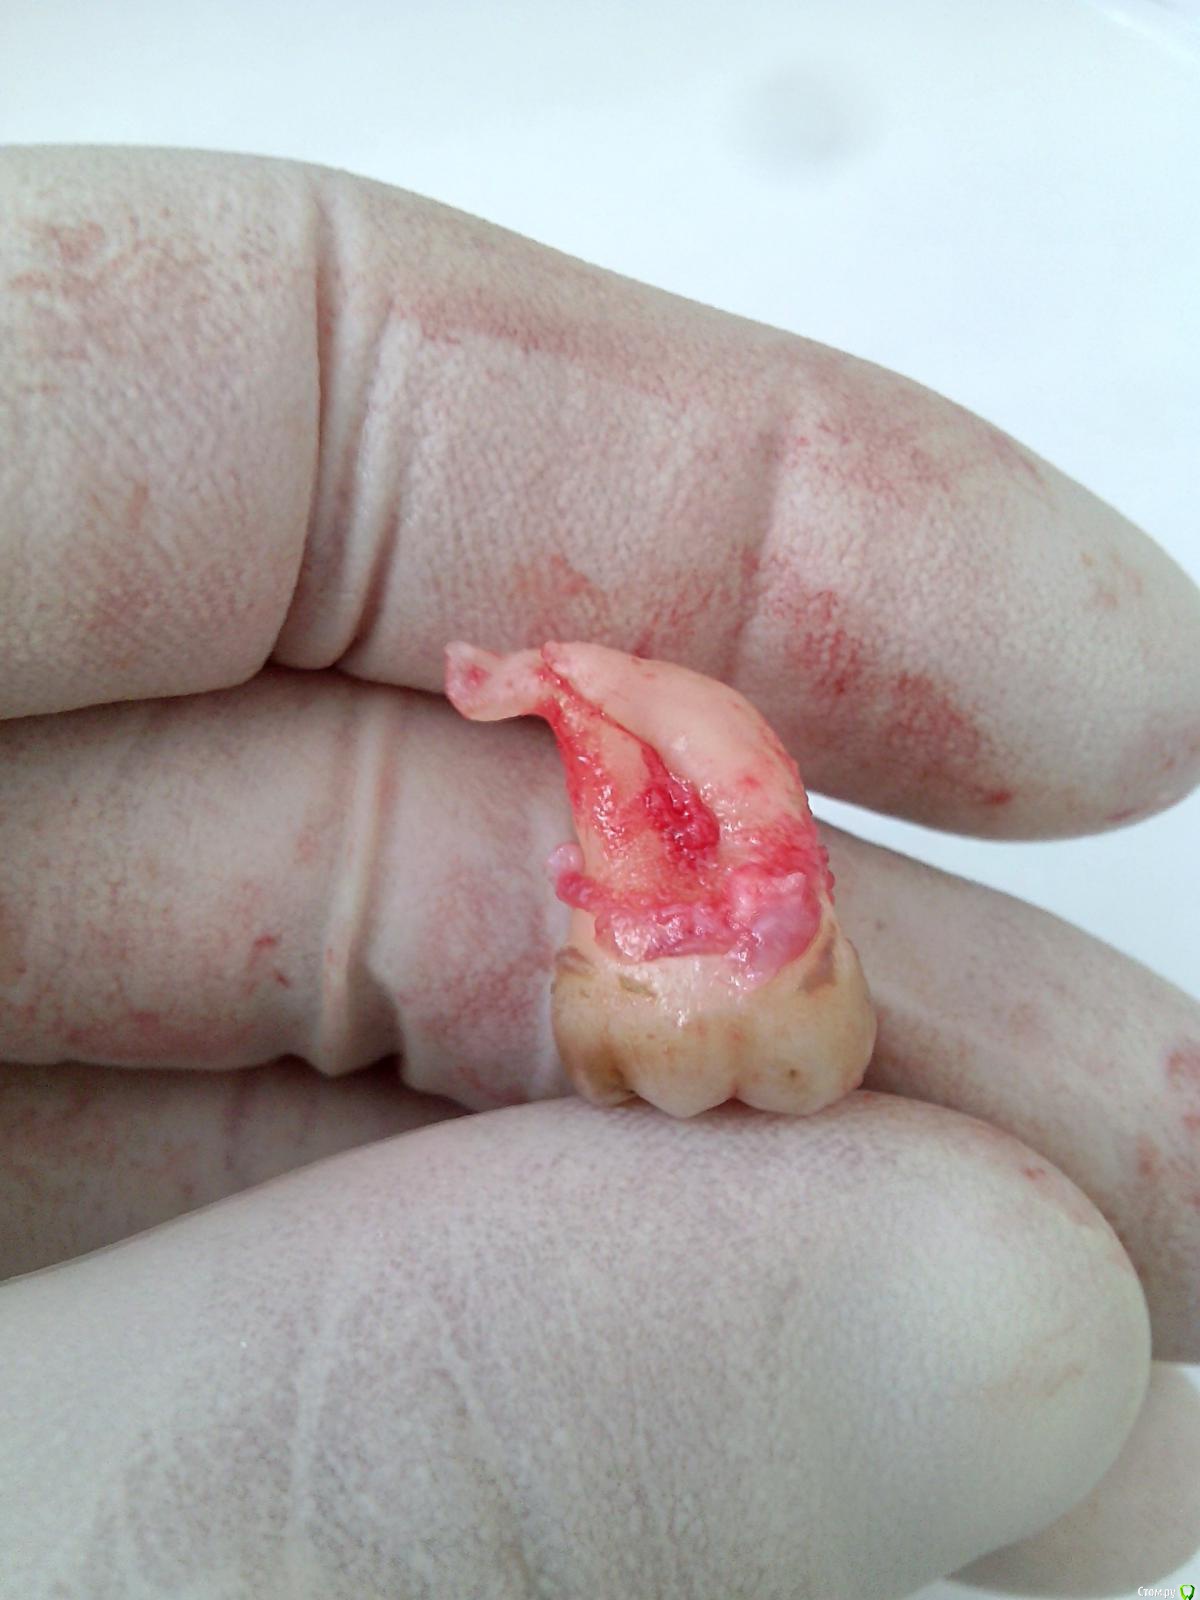

Doc Опубликовано 20 декабря, 2016 Поделиться Опубликовано 20 декабря, 2016 Всем доброго времени суток. Нужно удалить 48, не прорезался, в области медиальных бугров есть микросообщение с полностью рта, туда/оттуда подтекает.Начинаю убирать, все как обычно, оставшиеся корни хотят уйти, но им что то мешает, без резких движений чуть подтягиваю на себя корни и вижу что улов на крючке, точнее на корне, точнее между корней)Корни аккуратно разделил твердосплавом, все убрал, зашил. Парестезии нет, заживает без особенностей. Интересный был случий, разбавил рутину)Круто. Представляю что было бы с этим пациентом, если бы он пришел с этим зубом в какую-нибудь бесплатную поликлинику к доктору, у которого 30 номерков за час пройти должны. Ведь дернули бы и не заметили, что сделали человека инвалидом. 1 Ссылка на комментарий

PaulG Опубликовано 20 декабря, 2016 Поделиться Опубликовано 20 декабря, 2016 Всем доброго времени суток. Нужно удалить 48, не прорезался, в области медиальных бугров есть микросообщение с полностью рта, туда/оттуда подтекает.Начинаю убирать, все как обычно, оставшиеся корни хотят уйти, но им что то мешает, без резких движений чуть подтягиваю на себя корни и вижу что улов на крючке, точнее на корне, точнее между корней)Корни аккуратно разделил твердосплавом, все убрал, зашил. Парестезии нет, заживает без особенностей. Интересный был случий, разбавил рутину)...турбина, микромотор, повышайка?Просто любопытно, кто что предпочитает. Ссылка на комментарий

Kovalov Igor Опубликовано 24 января, 2017 Поделиться Опубликовано 24 января, 2017 Похоже на часть пищевода. ))карманище)) и зуб был подвижный , гнойный перикоронит Ссылка на комментарий

Dok22 Опубликовано 25 января, 2017 Поделиться Опубликовано 25 января, 2017 Скорее всего не карман а ретромалярная киста. 2 Ссылка на комментарий